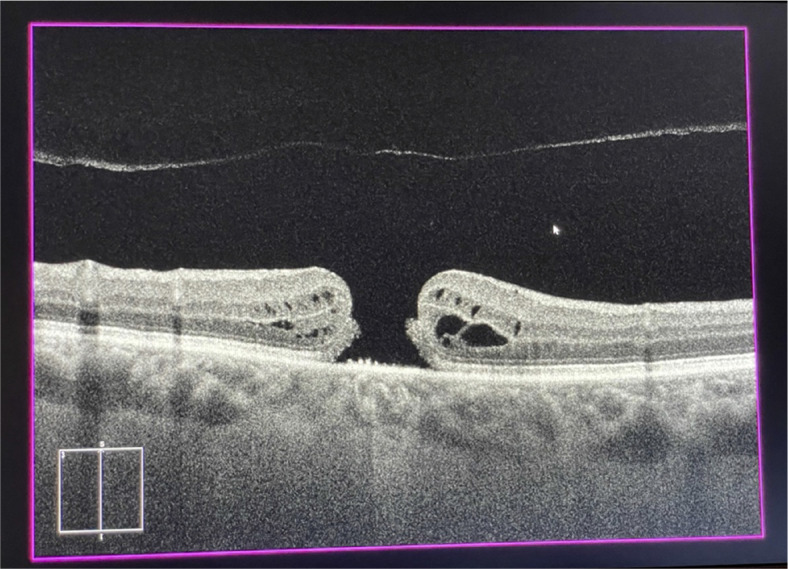

Surgical maculopathies: epiretinal membranes and full-thickness macular holes.